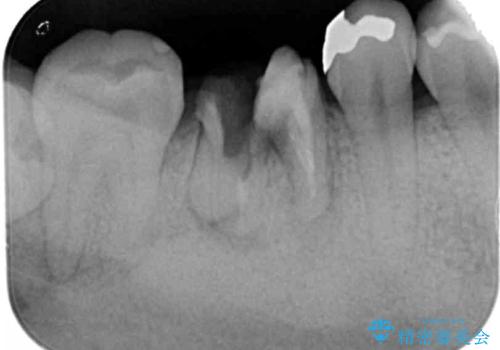

- 虫歯を数年放置した結果、痛みがひどくなり治療を希望され来院されました。

根だけ残った歯は、破折があり急性の炎症が認められ抜歯が必要な状態です。